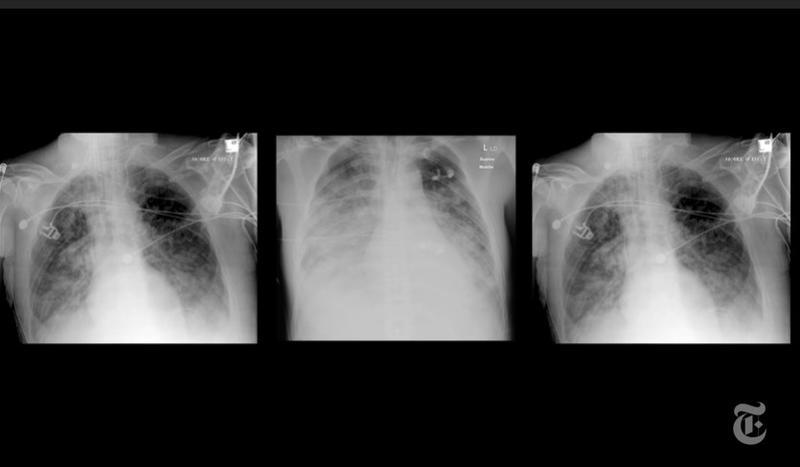

Medicii de la SCJU Arad atrag atenţia asupra gravităţii leziunilor pulmonare regăsite, în ultimele trei săptămâni, la pacienţii tineri infectaţi cu virusul SARS-CoV-2, care s-au prezentat târziu la spital Coronavirus NOV. '21 Medicii de la SCJU Arad atrag atenţia asupra gravităţii leziunilor pulmonare regăsite, în ultimele trei săptămâni, la pacienţii tineri infectaţi cu virusul SARS-CoV-2, care s-au prezentat târziu la spital